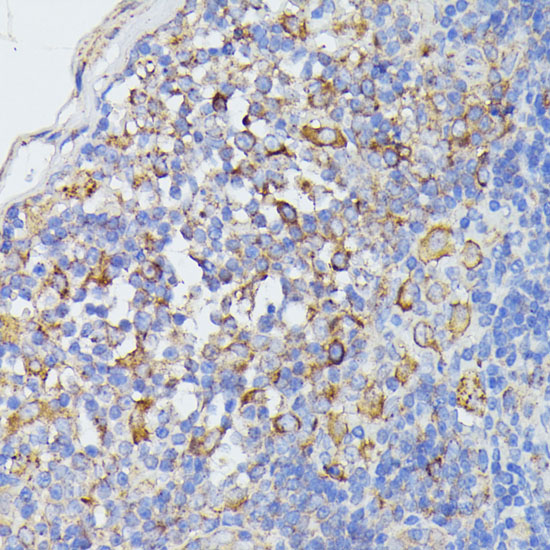

Immunohistochemistry of paraffin-embedded rat lymph node using STAT1 at dilution of 1:100 (40x lens).

Immunohistochemistry of paraffin-embedded mouse spleen using STAT1 at dilution of 1:100 (40x lens).